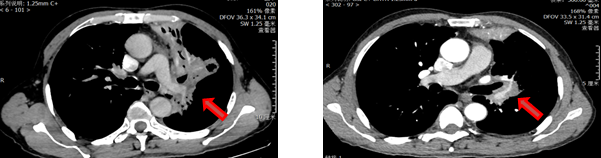

术前免疫+化疗后

经验总结,此例患者发现已经为局部晚期,肿瘤已经侵犯周围血管及主支气管,经过两个周期的免疫+化疗两个周期后,病灶明显缩小较,经手术治疗后达到完整切除,术后病理可见局部淋巴结转移,继续给与免疫+化疗两个周期。